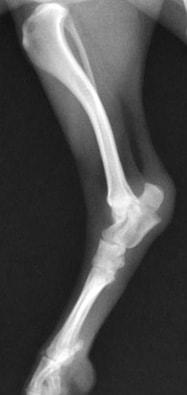

前肢の骨折:橈骨尺骨骨折

![]() 骨折時 |

![]() 手術後 |

![]() 骨折治癒 |

![]() 最後に金属の金具を取り除き完治 |